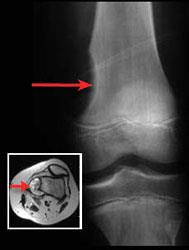

Bone tumor in the thigh

Femur (thighbone) tumor. This X-ray shows a tumor that caused a saucer-like erosion in the end of the thighbone. The insert shows the same tumor using a cross-sectional magnetic resonance image (MRI) scan.